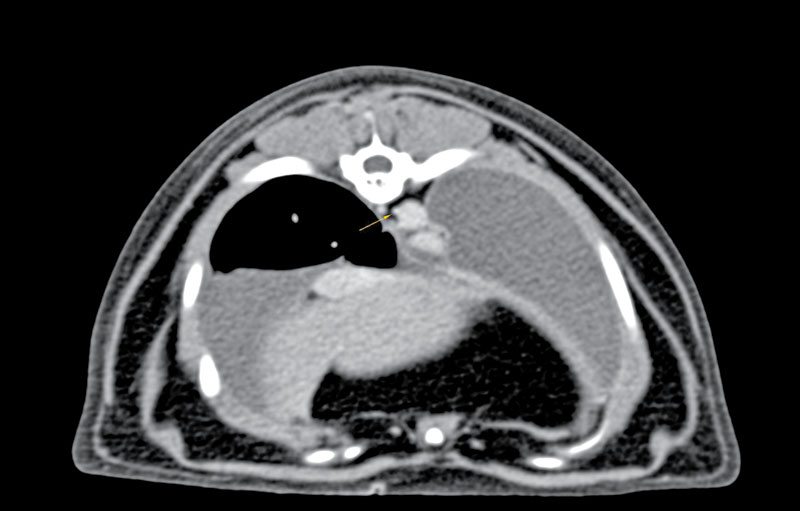

Prior to surgery, advanced imaging in the form of a CT scan combined with lymphangiography can be performed to better understand each patient's individual anatomy of the thoracic duct. Recent literature has described variations in the configuration of the thoracic duct among patients.21,22 Higher success rates may be achieved with patient-specific surgical planning, as additional branches and their location can be better identified (Figure 5). For the thoracoscopic approach to the thoracic duct, pre-operative imaging and planning are crucial for patient positioning and ideal port placement.

Figure 5. A CT scan image showing the thoracic duct located to the right of the aorta in a cat. This finding illustrates the benefit of advanced imaging for surgical planning. This cat had a right-sided thoracoscopic thoracic duct ligation. Photo courtesy CSU VTH Radiology